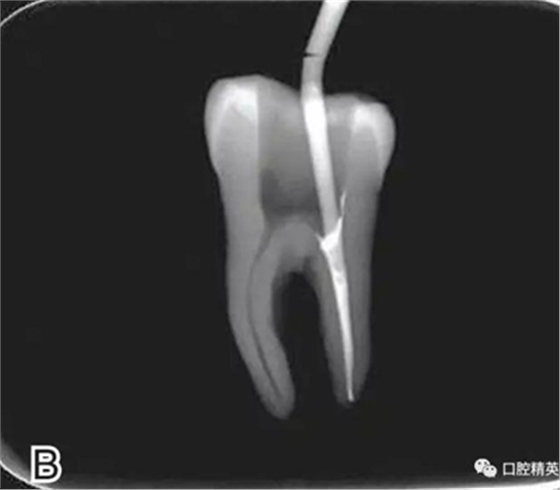

7、退出攜熱器工作尖

開啟加熱器1秒鐘,迅速退出攜熱器工作尖,帶出中上段多余牙膠尖。用小號垂直加壓器向下加壓,完成根尖段的充填(圖7)。

圖7 退出攜熱器工作尖,A.垂直加壓器加壓 B.根尖段的充填完成